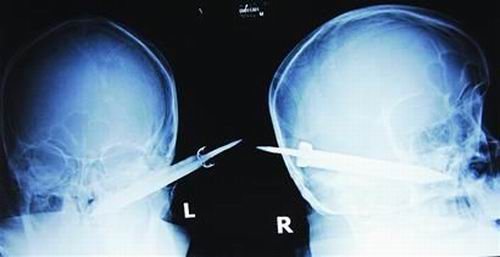

經(jīng)過檢查,醫(yī)生說這把長有10厘米左右的刀,從右耳窩上前方直接刺進了鼻腔,離頜內(nèi)大動脈很近,刀卡在了骨頭中,要取出這把刀最怕大出血,萬幸的是這把三棱刀并沒有傷及大腦。

截至昨晚11時30分,患者頭部刀經(jīng)手術(shù)已取出,生命體征平穩(wěn)。(芮瀟瀟)